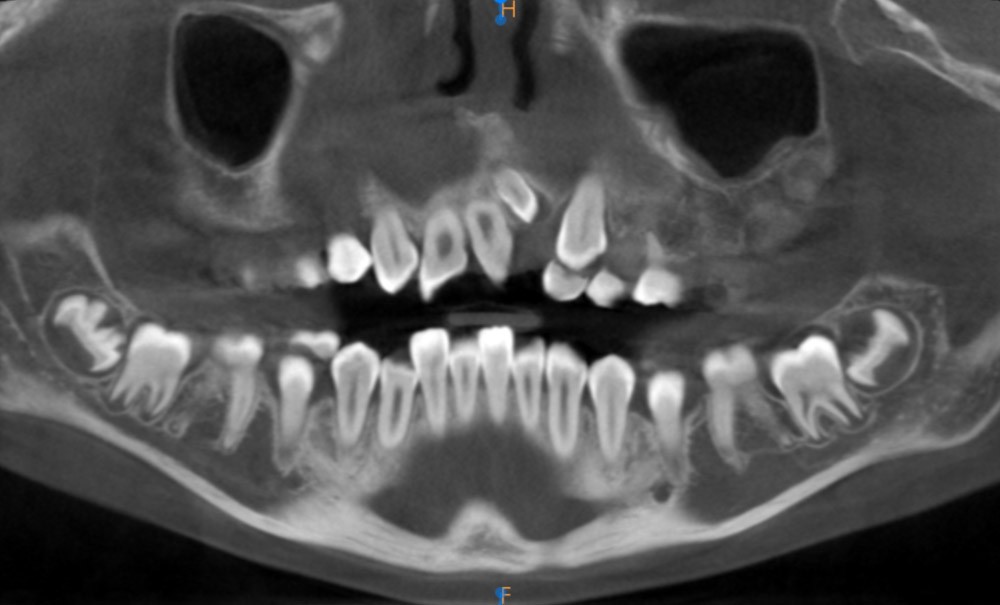

Information dentaire

En orthopédie dento-faciale, l’examen radiographique représente un examen complémentaire indispensable dans la démarche diagnostique. Cette dernière fait appel, habituellement, aux examens radiographiques conventionnels : la radiographie panoramique et la téléradiographie de profil. Ces deux techniques d’imagerie bidimensionnelles présentent plusieurs limites : un manque de perspective, des superpositions, des distorsions, des déformations… Ainsi, l’introduction des techniques d’imageries radiographiques tridimensionnelles (la tomographie à faisceau conique ou « cone beam » – CBCT – et le scanner – CT) a permis de pallier ces limites, constituant une sorte de révolution dans la démarche diagnostique en dentisterie de manière générale et en orthodontie en particulier [1, 2].

Bien que la résolution et la qualité d’image obtenues avec le CT soient meilleures, le CBCT est devenu la technique tridimensionnelle de choix en orthopédie dento-faciale en raison de ses différents avantages [1, 3, 4]. D’une part, il représente une technique d’imagerie relativement moins irradiante que le CT. D’autre part, il nécessite un investissement moins important pour le praticien : le coût est moindre et l’équipement est moins encombrant [5]. Cependant, selon plusieurs auteurs et institutions, le CBCT reste une technique relativement plus irradiante en comparaison des techniques radiographiques bidimensionnelles et ne peut donc constituer un examen radiographique de routine.